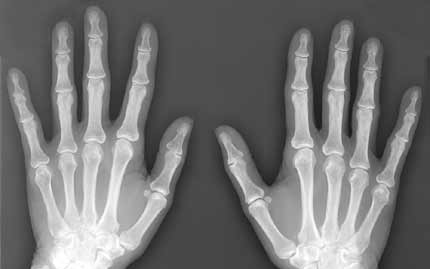

A magzatvízben lévő őssejtek újjáéleszthetik az öregedő és gyenge csontokat - állítják brit kutatók, akik szerint felfedezésük segíthet genetikai betegséggel született gyerekeken, idős embereken és űrhajósokon is.

A londoni Great Ormond Street Hospital és a University College London együttműködéséből született Gyermekegészségi Intézet szakemberei súlyos genetikai betegségben, üvegcsontúságban (osteogenesis imperfecta) szenvedő egerekbe fecskendezték be a mintákból kinyert őssejteket.

Az emberek esetében nagyjából minden huszonötezredik csecsemő ezzel a betegséggel, vagyis többszörös csonttöréssel jön a világra. Azok, akik túlélik, a későbbiekben akár évi 15 csonttörést is szenvedhetnek, fogaik törékenyek, hallásuk rossz lehet és fejlődési problémákkal is küzdhetnek.

Az egereken végzett vizsgálatok azt mutatták, hogy az őssejtek befecskendezésével az állatok csontjai megerősödtek, és rugalmasságuk, valamint szerkezetük is javult. A csonttörések száma 80 százalékkal csökkent.

A csontok folyamatos átépüléséért a csontfaló sejtek (osteoclast) és a csontképző sejtek (osteoblastok) a felelősek. Guillot szerint az üvegcsontúság, a csontritkulás és az űrutazásokkor bekövetkező csonttörések hátterében a csontképző sejtek "ellustulása" áll.

Az eredmények szerint a magzatvízből nyert őssejtek növelték a csontképző sejtek természetes aktivitását, ahelyett, hogy közvetlenül maguk hoztak volna létre új csontokat.